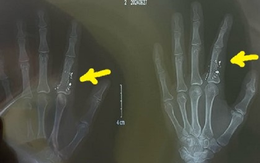

HI HỮU: Cháu bé bị nhiễm độc thủy ngân khi đo thân nhiệt

TTO - Chiều 27-2, thông tin từ Bệnh viện Bạch Mai cho biết khoa nhi và Trung tâm Chống độc của bệnh viện đang điều trị cho một cháu bé bị nhiễm độc thủy ngân qua da do người nhà vẩy nhiệt kế thủy ngân chọc trúng tay trẻ.